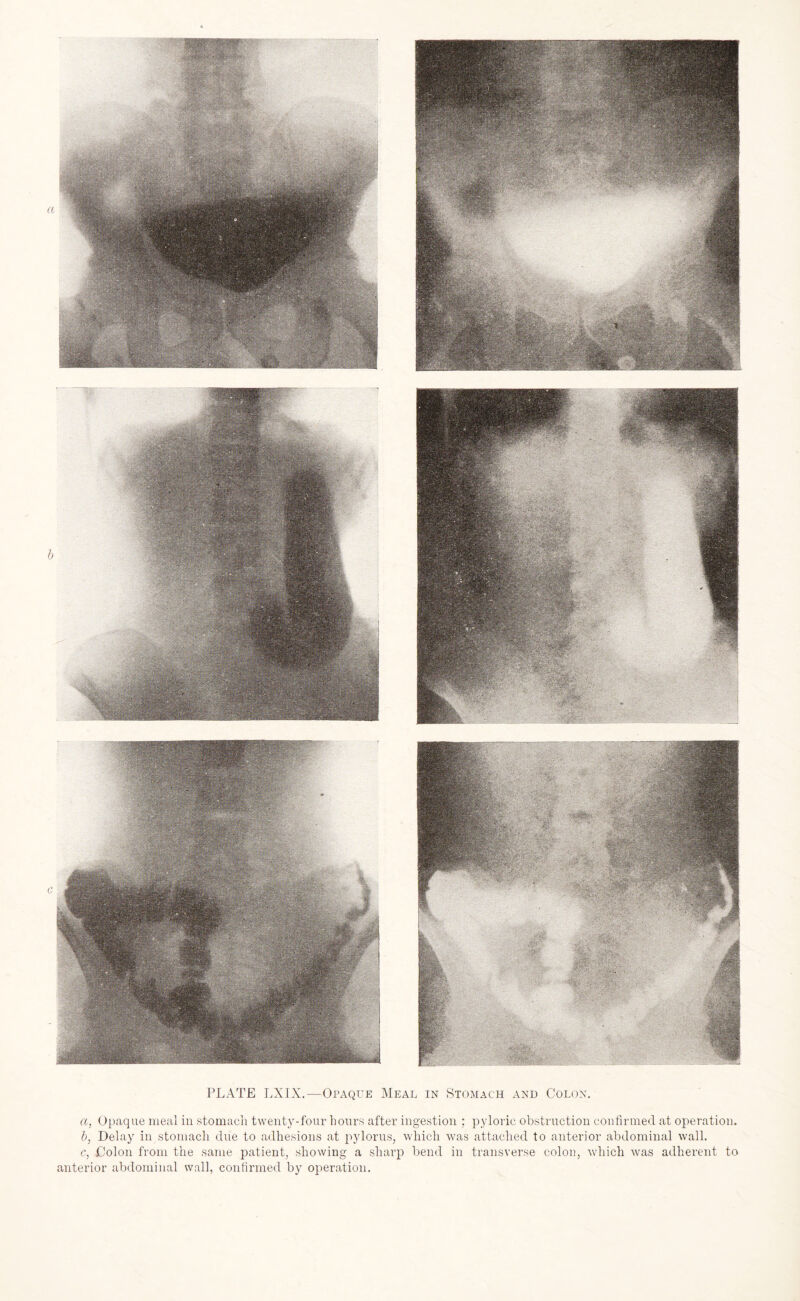

462/544 page 350